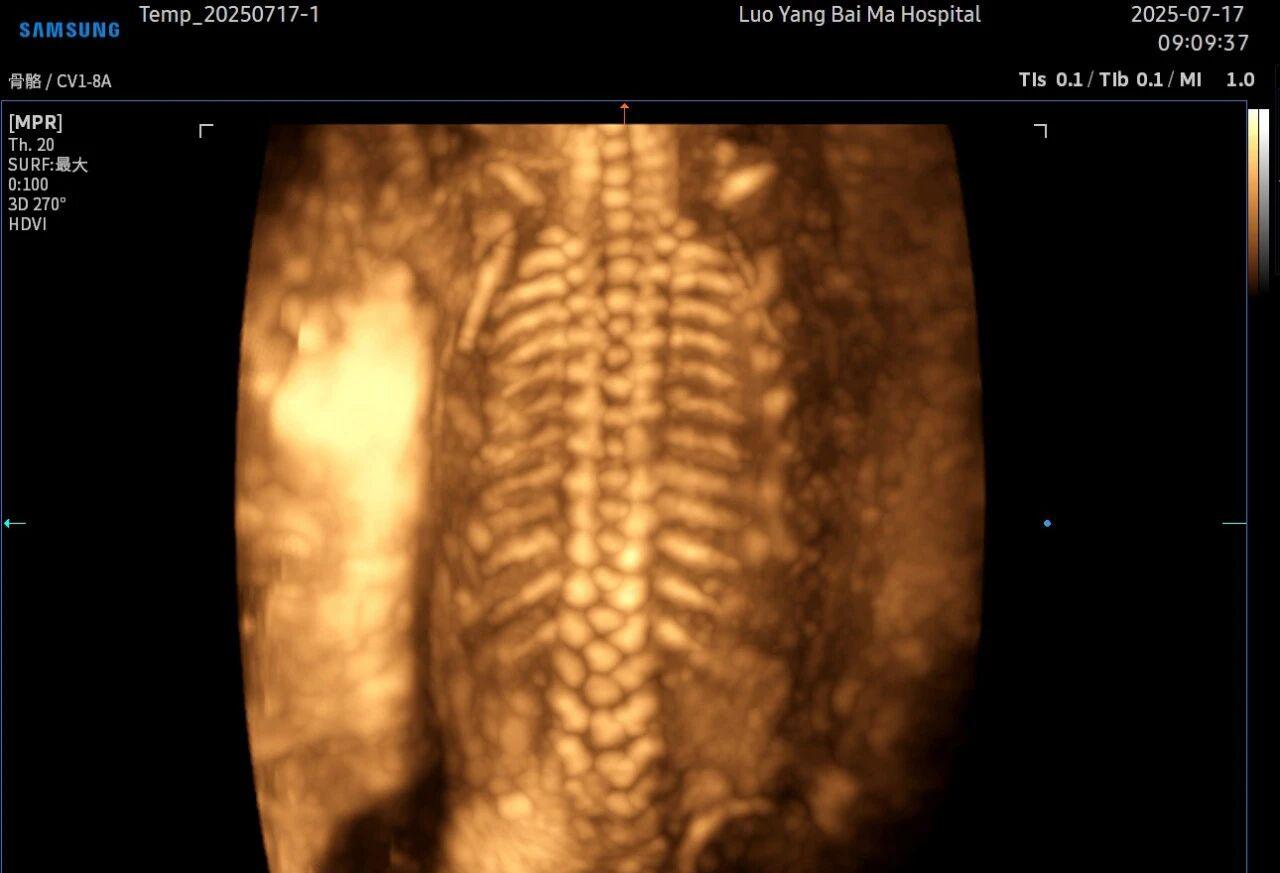

5D智能彩超拥有更高的分辨率和更强的图像处理能力,能够呈现出接近“IMAX电影画质”的细腻影像 。它采用一种被称为“水晶成像”的技术,能够穿透组织,将胎儿的骨骼、器官和组织结构以极其清晰、立体的形态展示出来。这种高清晰度对于观察胎儿微小的解剖结构细节至关重要,例如手指、脚趾、耳廓形态等,有助于医生发现一些在传统超声下不易察觉的细微异常,为排畸诊断提供了更丰富的视觉信息。

传统超声检查有时会因为胎儿体位、羊水量等因素的限制,导致某些部位观察不清。5D智能彩超技术能够实现对目标结构进行360°全方位、多切面的自由旋转观察。医生可以像“雕塑家”一样,从任意角度审视胎儿的解剖结构,尤其对于形态复杂的心脏、颅脑和脊柱等部位,这种能力可以极大弥补单一平面的局限性,帮助医生更全面地评估其发育状况。